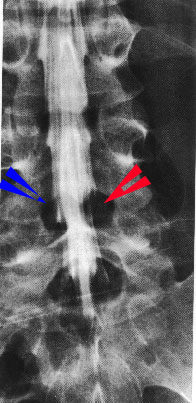

左の図は椎間板ヘルニアの方の脊髄腔造影を正面から見たものです。

図の中で青い矢印のところは神経根が造影されていますが、その対象となるところの赤い矢印のところの神経根が造影されていないことに注目して下さい。

ヘルニアによって神経根が圧迫されてしまい造影剤が神経根の袋に入らないために写ってこないのです。